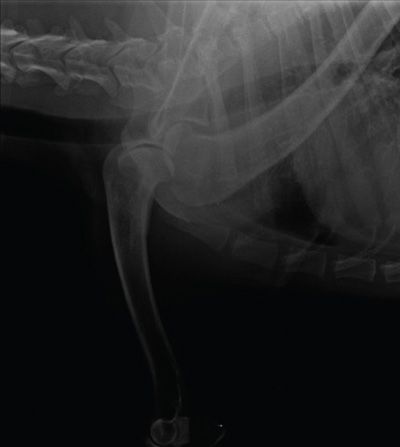

In DR systems, overexposure of radiographs often leads to saturation of the detector that reduces the ability of the pixels to differentiate grey tonal variation and can lead to a flat, poor contrast image and, in extreme cases, visualisation of the calibration mask of the detector (Figure 1). It should also be remembered that the photostimulable phosphors (PSP) of CR systems are very prone to backscatter and, if high exposures are used, will result in grey, flat images (Figure 2). The PSP plates of the CR system also need to be erased prior to any exposure and may require a double erasure if high exposure factors have been used to reduce poor contrast images and the risk of ghost images being present (Figure 3).

Figure 2. Mediolateral view of the shoulder (CR image): The radiograph of the shoulder is overexposed with poor positioning ( second shoulder superimposing) and inadequate collimation. The high exposure and large area in the primary beam have resulted in the generation of a lot of backscatter which PSP plates are very sensitive to, resulting in an image that is overly dark and grey with poor contrast.